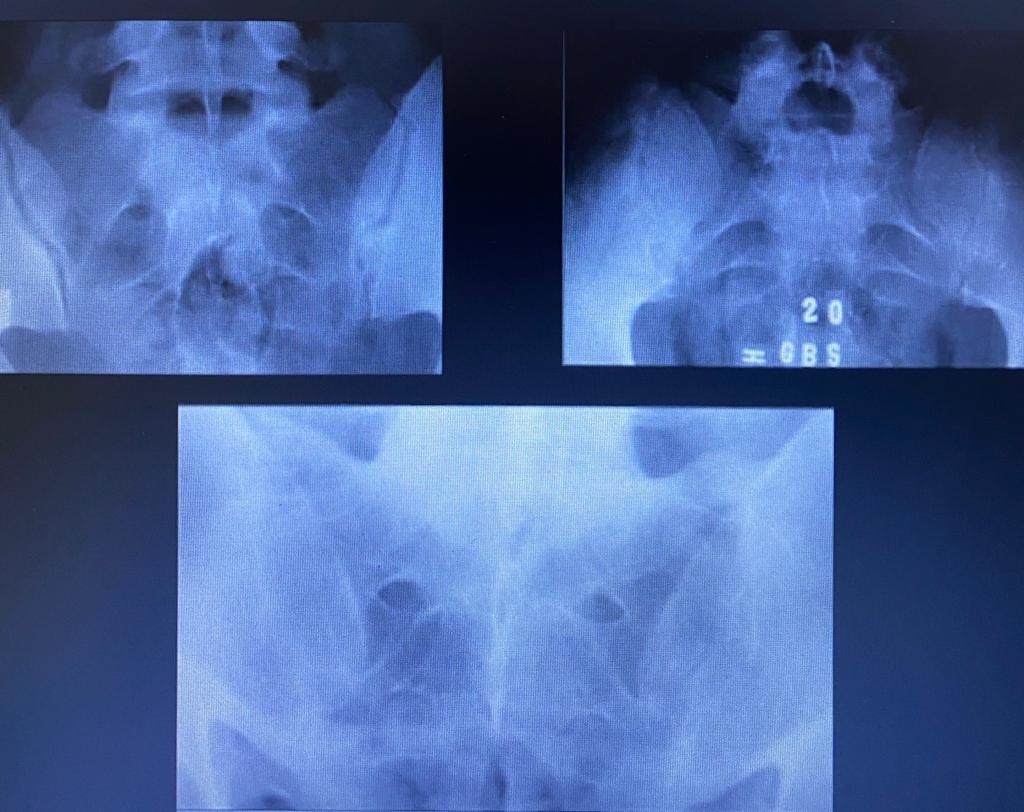

ESPONDILITE ANQUILOSANTE

Entesite calcificante crônica ascendente que sempre começa com sacroiléite, formando pontes ósseas (sindesmófitos)

Diagnóstico: dor lombar crônica + sacroiléite OU HLA-B27

Imagem: calcificação sacro-iliaca, coluna em bambu, osteofitos calcâneo

Tratamento: parar de fumar, aines, fisioterapia, anti-TNF alfa (infliximabi)